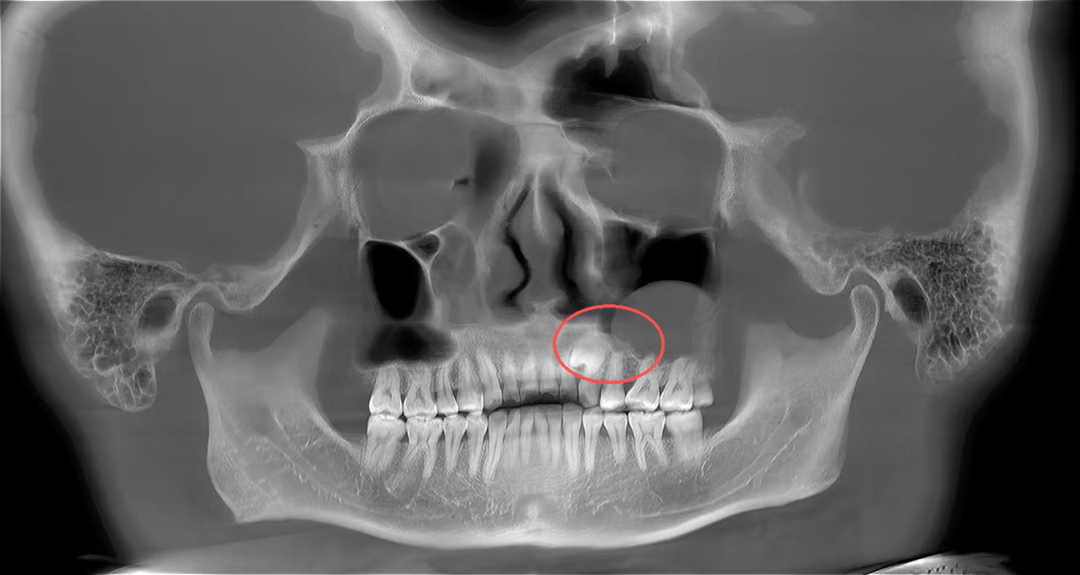

口腔颌面外科医生为其进行了详细的口腔检查并拍了放射片,结果显示:张先生的牙齿属于腭向埋伏阻生双尖牙,更值得注意的是,他的左侧上颌窦底还长有一个丘状软组织囊肿,且阻生牙的牙根与囊肿底部关系十分密切。

“阻生牙是牙齿萌出过程中因空间不足、遗传、感染等多种因素导致的异位埋伏,而上颌窦囊肿则是上颌窦内常见的良性病变,两者同时出现且位置紧密关联,若不及时处理,可能会引发囊肿增大、骨质破坏、上颌窦炎等问题。”口腔颌面外科病房主任孙超解释道。

术后4个月,张先生复查时,伤口已经愈合得很好,没有任何不适,也没出现上颌窦炎等问题。拍片显示,上颌窦里的囊肿完全消失,拔牙的地方也长出了新骨头。